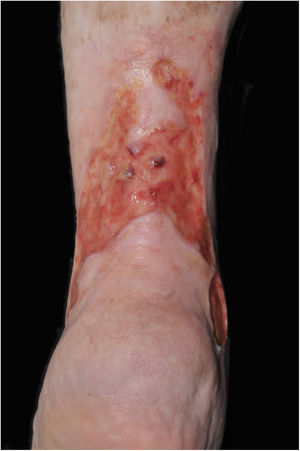

At the initial examination, an ulcer in the posterior and lateral regions of the LLL was observed with 15×8cm, wound bed with a fibrotic and devitalized tissue, without signs of colonization, edge not adhered to the bed (Fig. 1). The ulcer presented serous exudation and local pain with moderate intensity. Palpable distal pulses 4+/4+. MEC was initiated (Fig. 2) with exchange of dressings twice a week for the first three weeks due to high exudation and saturation of the dressing and, thereafter, once a week. On the first 20 days, the VU became shallower, with partially vitalized bed and edges adhered to the wound bed, making possible the spacing of the dressing changes. In a three-month period, there was a significant improvement in the quality of the ulcer wound bed and a decrease in the ulcerated area until completes healing (Fig. 3). High compression elastic stockings were prescribed to prevent relapse.